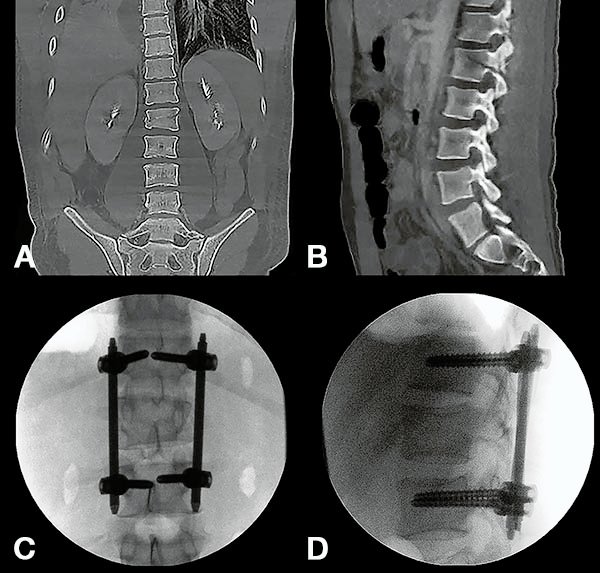

Figura 2:

Caso 24. A y B: Fractura horizontal que compromete cuerpo, pedículo izquierdo y apófisis espinosa de L1 (L1: B1; N1 AOSpine). C y D: Estabilización percutánea T12-L2.

Figura 3:

Caso 24. A: Fractura L1: B1; N1. B: Control 7 meses que evidencia consolidación. C y D: Retiro de osteosíntesis a los 9 meses con buena movilidad en las radiografías dinámicas de control.